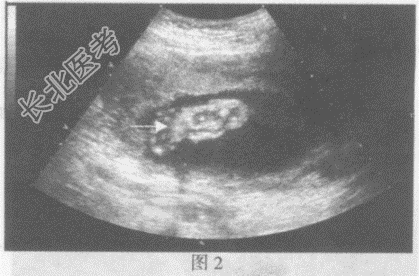

- 单项选择题请指出下图箭头所指的是胎儿哪个部位:

A、图1:胎儿股骨长径,图2:脚

B、图1:胎儿胫骨长径,图2:手

C、图1:胎儿肱骨长径,图2:面部

D、图1:胎儿桡骨长径,图2:颈部

E、图1:胎儿桡骨长径,图2:脊柱